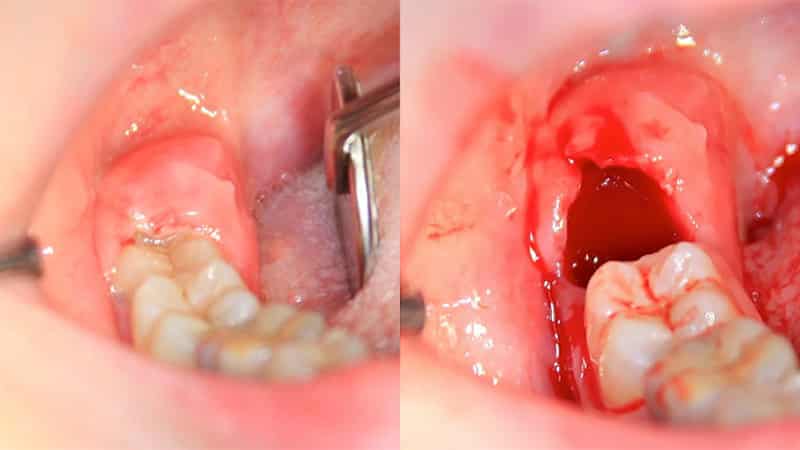

Возможные осложнения при атипичной тракции

К сожалению, стандартное удаление зуба мудрости на верхней челюсти, которое обычно проходит без серьезных последствий, не всегда возможно. Часто наблюдаются ситуации, когда корни восьмого зуба проникают в гайморову пазуху. В таких случаях, если удаление зуба проходит травматично, это может привести к повреждению пазухи или случайному попаданию обломков в нее. Игнорировать такие последствия нельзя, так как это может привести к образованию кисты в пазухе, а в дальнейшем — к хроническому гаймориту, который можно будет устранить только хирургическим вмешательством.

Еще одним примером сложного удаления является перелом альвеолярного отростка. Это происходит, как правило, когда моляр находится в крайнем положении относительно кости. В результате извлечения восьмерки может произойти отслоение костной ткани десны.

К возможным осложнениям также относится случайное повреждение мягких тканей полости рта, что может привести к их инфицированию. Обычно это происходит, когда извлечь моляр целиком не удается, и стоматолог вынужден удалять его по частям. Такие действия могут привести к частичному удалению, когда верхняя часть корня остается незамеченной в десне.

Эти ситуации часто возникают из-за отсутствия рентгеновского снимка челюсти, а также при запущенных и необратимых процессах разрушения пульпы. Безусловно, такие случаи не редкость, но квалифицированный стоматолог и внимательный подход пациента к процедуре помогут минимизировать все возможные риски.